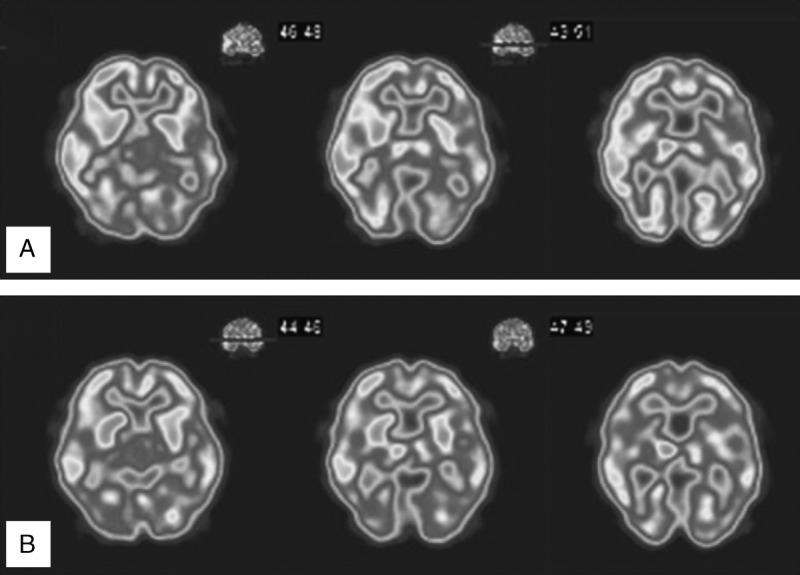

We present 2 cases of oral cenesthopathy, who responded well to aripiprazole. The asymmetric rCBF patterns were attenuated after successful treatment in both cases.

We found a marked improvement of oral cenesthopathy with aripiprazole. It is suggested that right > left rCBF asymmetry in the frontal and temporal lobes and thalamus, and the dopaminergic and serotonergic dysfunctions are involved in the pathology of oral cenesthopathy.

口腔感觉异常是指在无法确定潜在器质性病因的情况下出现的口腔异常感觉。它也被称为口腔感觉障碍或口腔躯体妄想,归类为妄想障碍,躯体型。口腔感觉异常患者在广泛的脑区表现出右侧>左侧不对称的局部脑血流(rCBF)。然而,迄今为止,对成功治疗前后rCBF变化进行仔细研究的仍为数不多。

我们报告2例口腔感觉异常患者,他们对阿立哌唑反应良好。在两例患者成功治疗后,不对称的rCBF模式均有所减轻。

我们发现阿立哌唑可显著改善口腔感觉异常。提示额叶、颞叶和丘脑的右侧>左侧rCBF不对称以及多巴胺能和5-羟色胺能功能障碍与口腔感觉异常的病理机制有关。